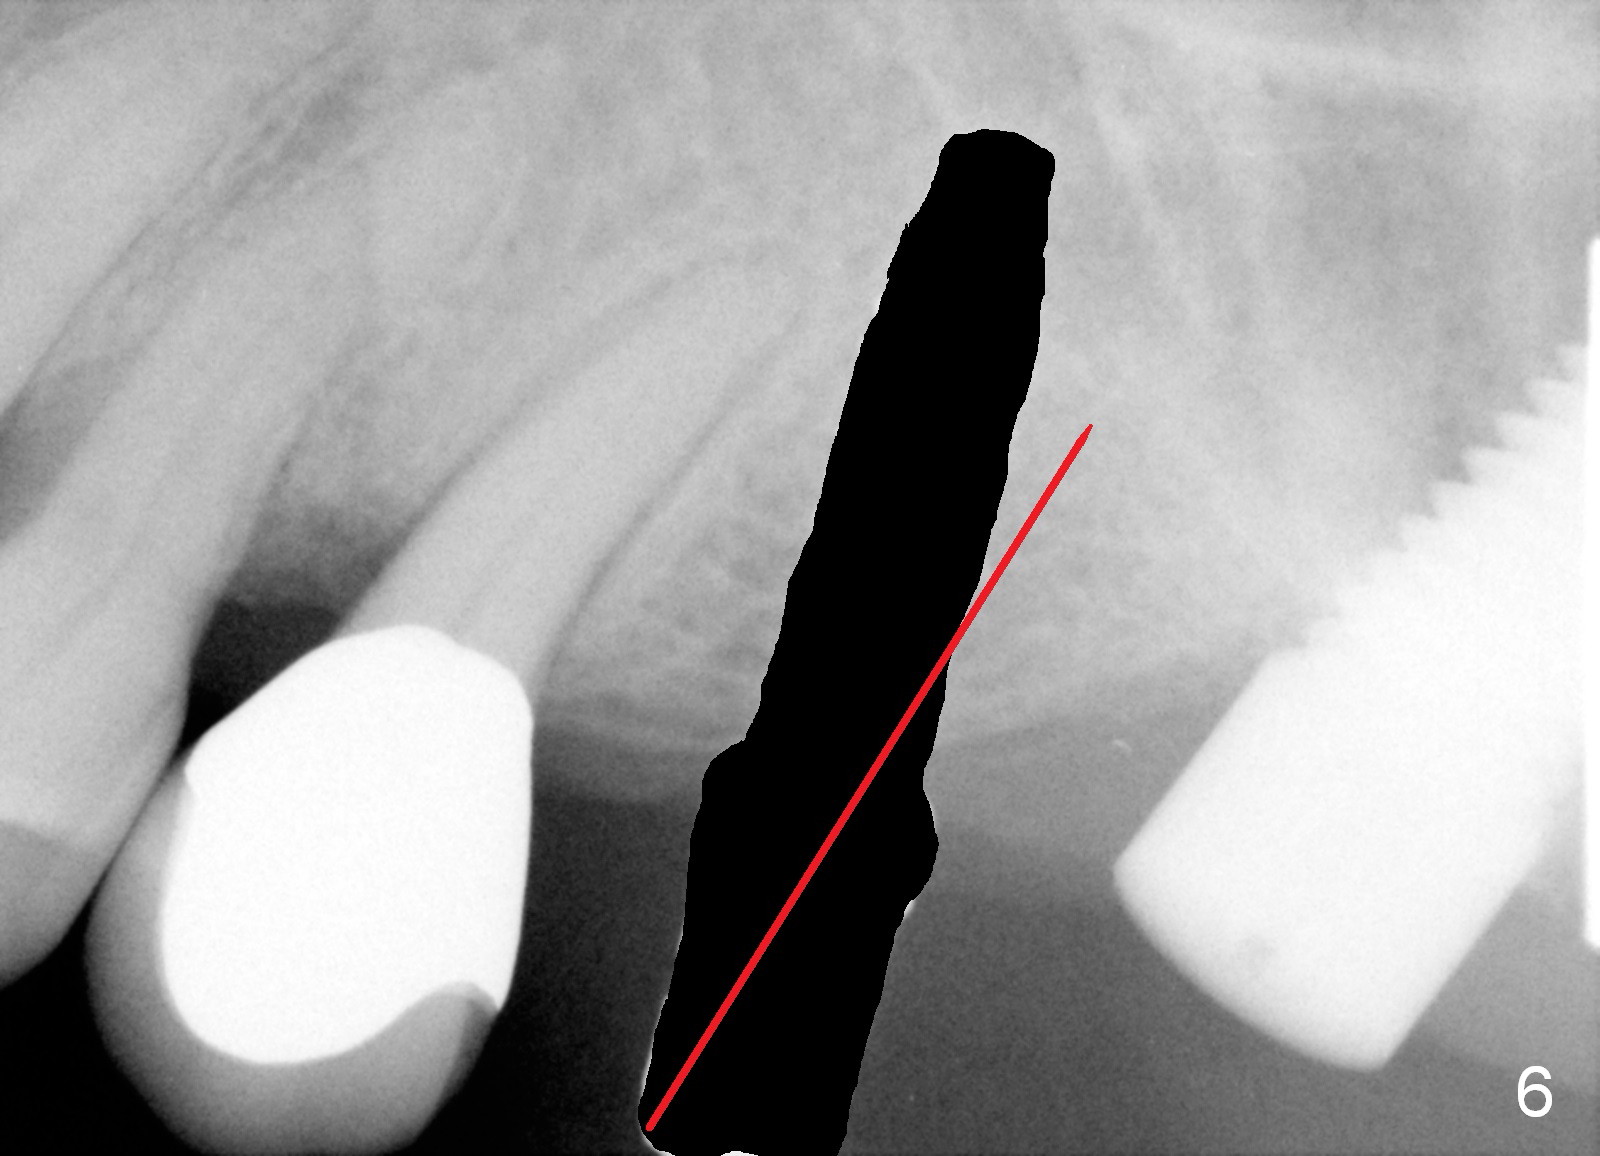

A 58-year-old man used to have a upper left 3-unit bridge. Two months after extraction and immediate implant at the site of the posterior abutment, an implant is planned to be placed at the site of the pontic, #14 (Fig.1). Osteotomy starts with a 1.6 mm pilot drill, followed by bone expanders, parallel to the crown of the tooth #13. The first intraop PA shows that 3.0 mm bone expander is close to the root of the neighboring tooth (Fig.2). No matter what is done to change the trajectory of the osteotomy using expanders according to the crown morphology of the neighboring tooth, the next 3 expander does not improve in parallelism (Fig.3). When a 6x17 mm tap is inserted (Fig.4 T), it is realized that axis of the tap is parallel to the axis of the crown of the neighboring tooth (black line), but not that of the root (red line). It is too late to change the trajectory drastically; a 6x17 mm implant is placed with insertion torque > 60 Ncm (Fig.5). It is best to change the trajectory as early as possible, e.g., after taking the first intraop PA and withdrawing the expander (Fig.6 black area) and as much as possible (red line; starting new osteotomy). It is quite similar to immediate implant. There is no bone loss 2 months postop (Fig.7), 18 months (Fig.8,9) or 34 months (Fig.10)post cementation, in spite of open contact between the crowns (Fig.10 black arrowhead). This is partially due to supragingival margin (Fig.11,12 (immediately pre-cementation)). No bone loss is noted 3 years 5 months post cementation (Fig.13).

In contrast, the trajectory of an immediate implant could be changed almost anytime and much easier. An immediate implant is always larger than non-immediate one at similar sites.